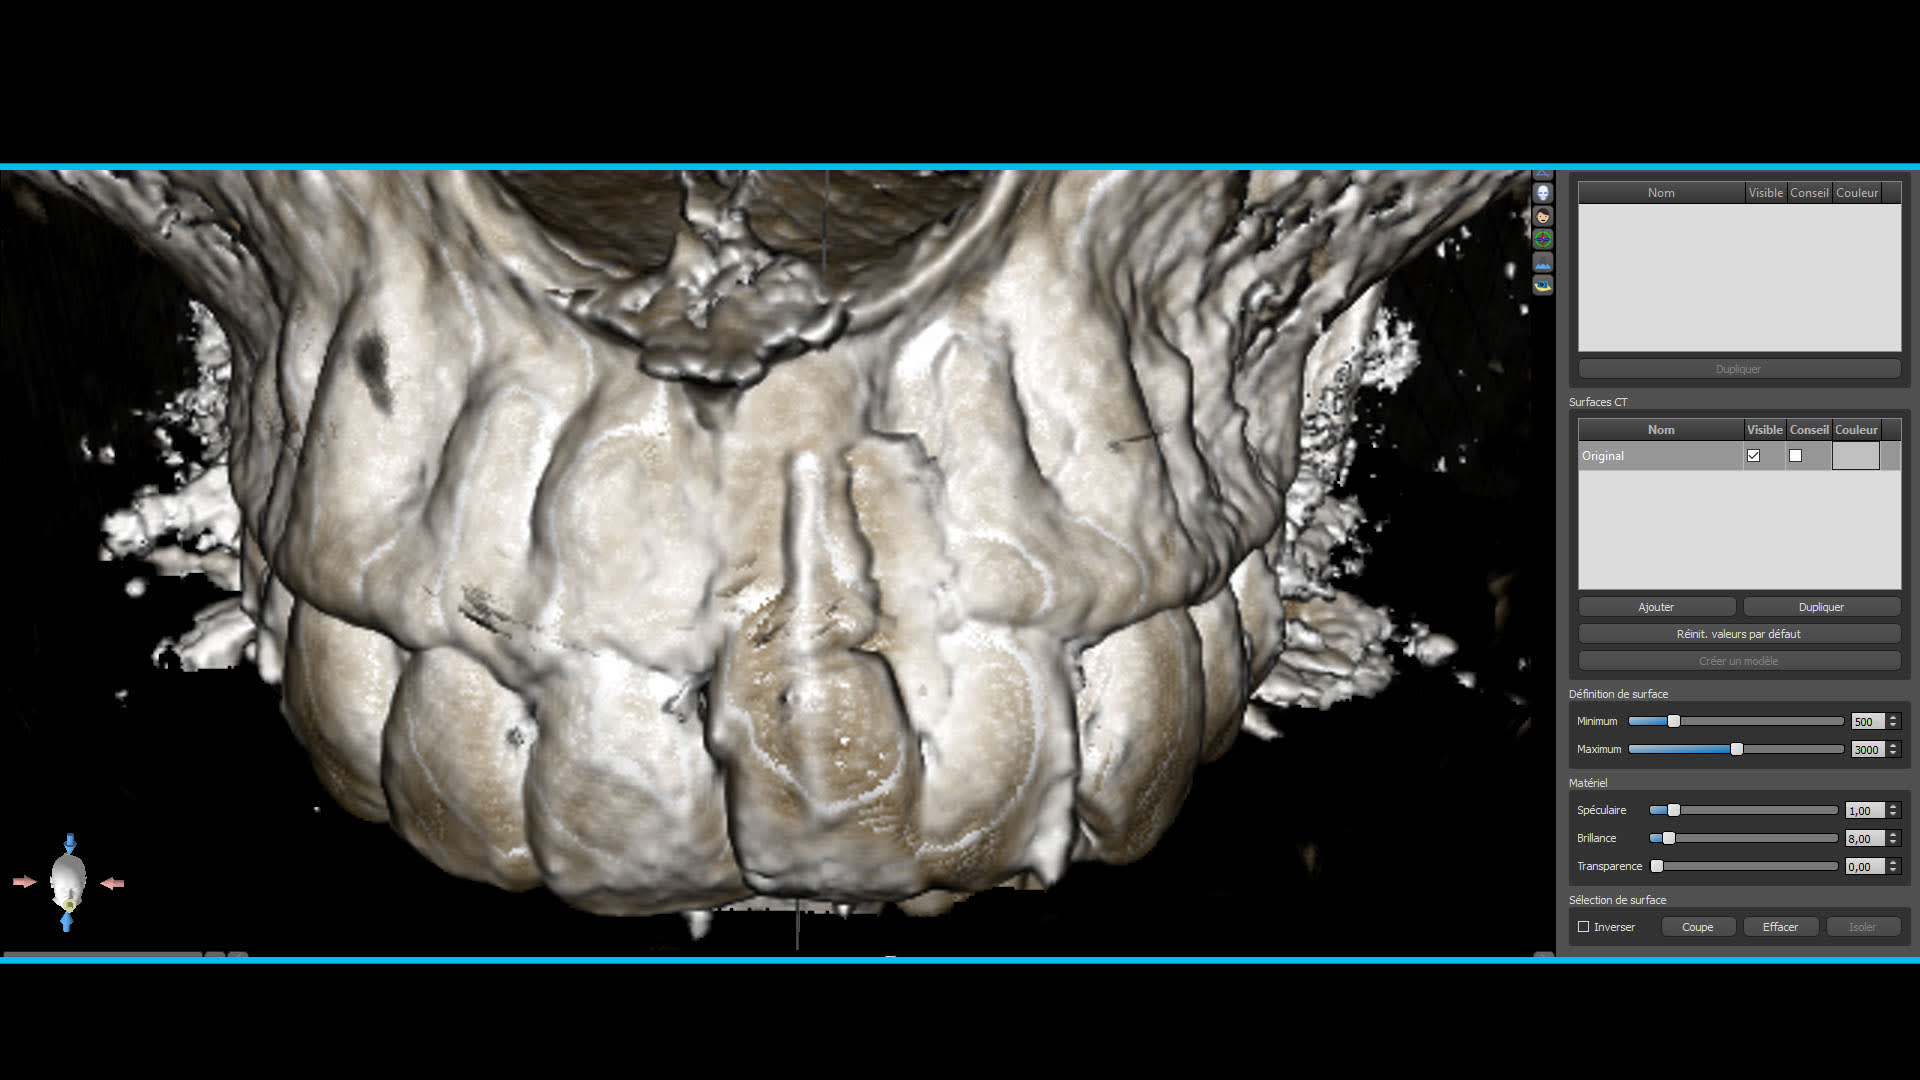

Quelques images du cone beam et de la planif

Planif 1 owxhvi - Eugenol

Planif 2 slmeas - Eugenol

Planif 3 v71j9j - Eugenol

Planif 4 my2dza - Eugenol

Planif 5 fqtf2p - Eugenol

Planif 6 ody3rj - Eugenol

Euh... ton implant est très très enfoui esthétiquement je pense que ça va pas être une super surprise (même si elle recouvre, pense que les patients regardent toujours en soulevant la lèvre...) ensuite par rapport à l'apex de ta 11 il semble très haut, je ferai une 3D perso pour voir mon plancher des fosses nasales.